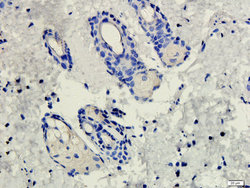

- Submitted by

- antibodies-online (provider)

- Main image

- Experimental details

- IHC